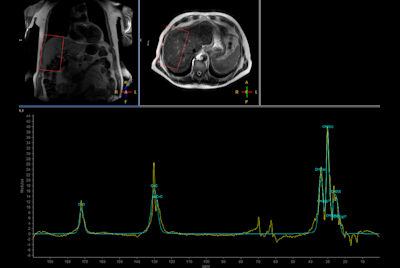

Multi Nuclei - Dynamic calf muscle imaging (31P)